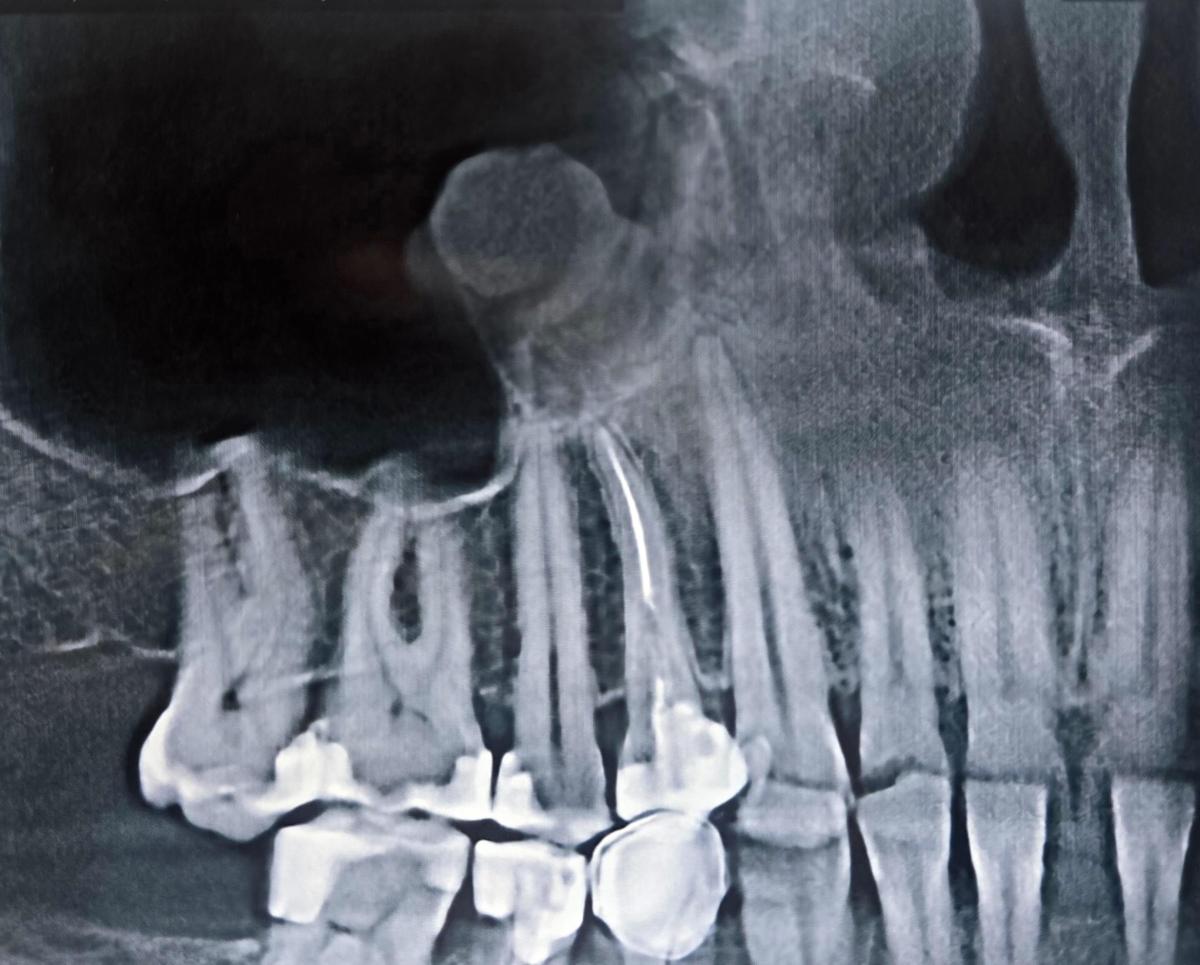

Кстати, на клкт у четверки по описанию рентгенолога

"каналы заполнены пломбировочным материалом на всём протяжении, на уровне средней неоднородно, с дефектами; отмечается выведение небольшого фрагмента пломбировочного материала за апикальное отверстие небного канала."

Похоже, этот зуб основной кандидат. Причем тут целых 2 фактора - каналы и материал за апексом. Но, похоже, скорее каналы

у зуба, которы слева от запломбираванного, присутствует

"в центральной и мезиальной части коронки выраженное снижение радиологической плотности дентина, истончение эмали по мезиальной поверхности"

Но это не попало в сечение на снимке, а второй прикрепить не смог